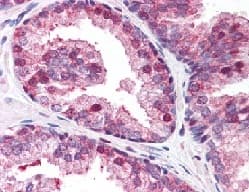

Rabbit Polyclonal GOLPH3/MIDAS antibody. Suitable for WB, IHC-P and reacts with Rat, Human samples. Cited in 1 publication. Immunogen corresponding to Synthetic Peptide within Human Golgi phosphoprotein 3 conjugated to Keyhole Limpet Haemocyanin.

Applications IHC-P, WB